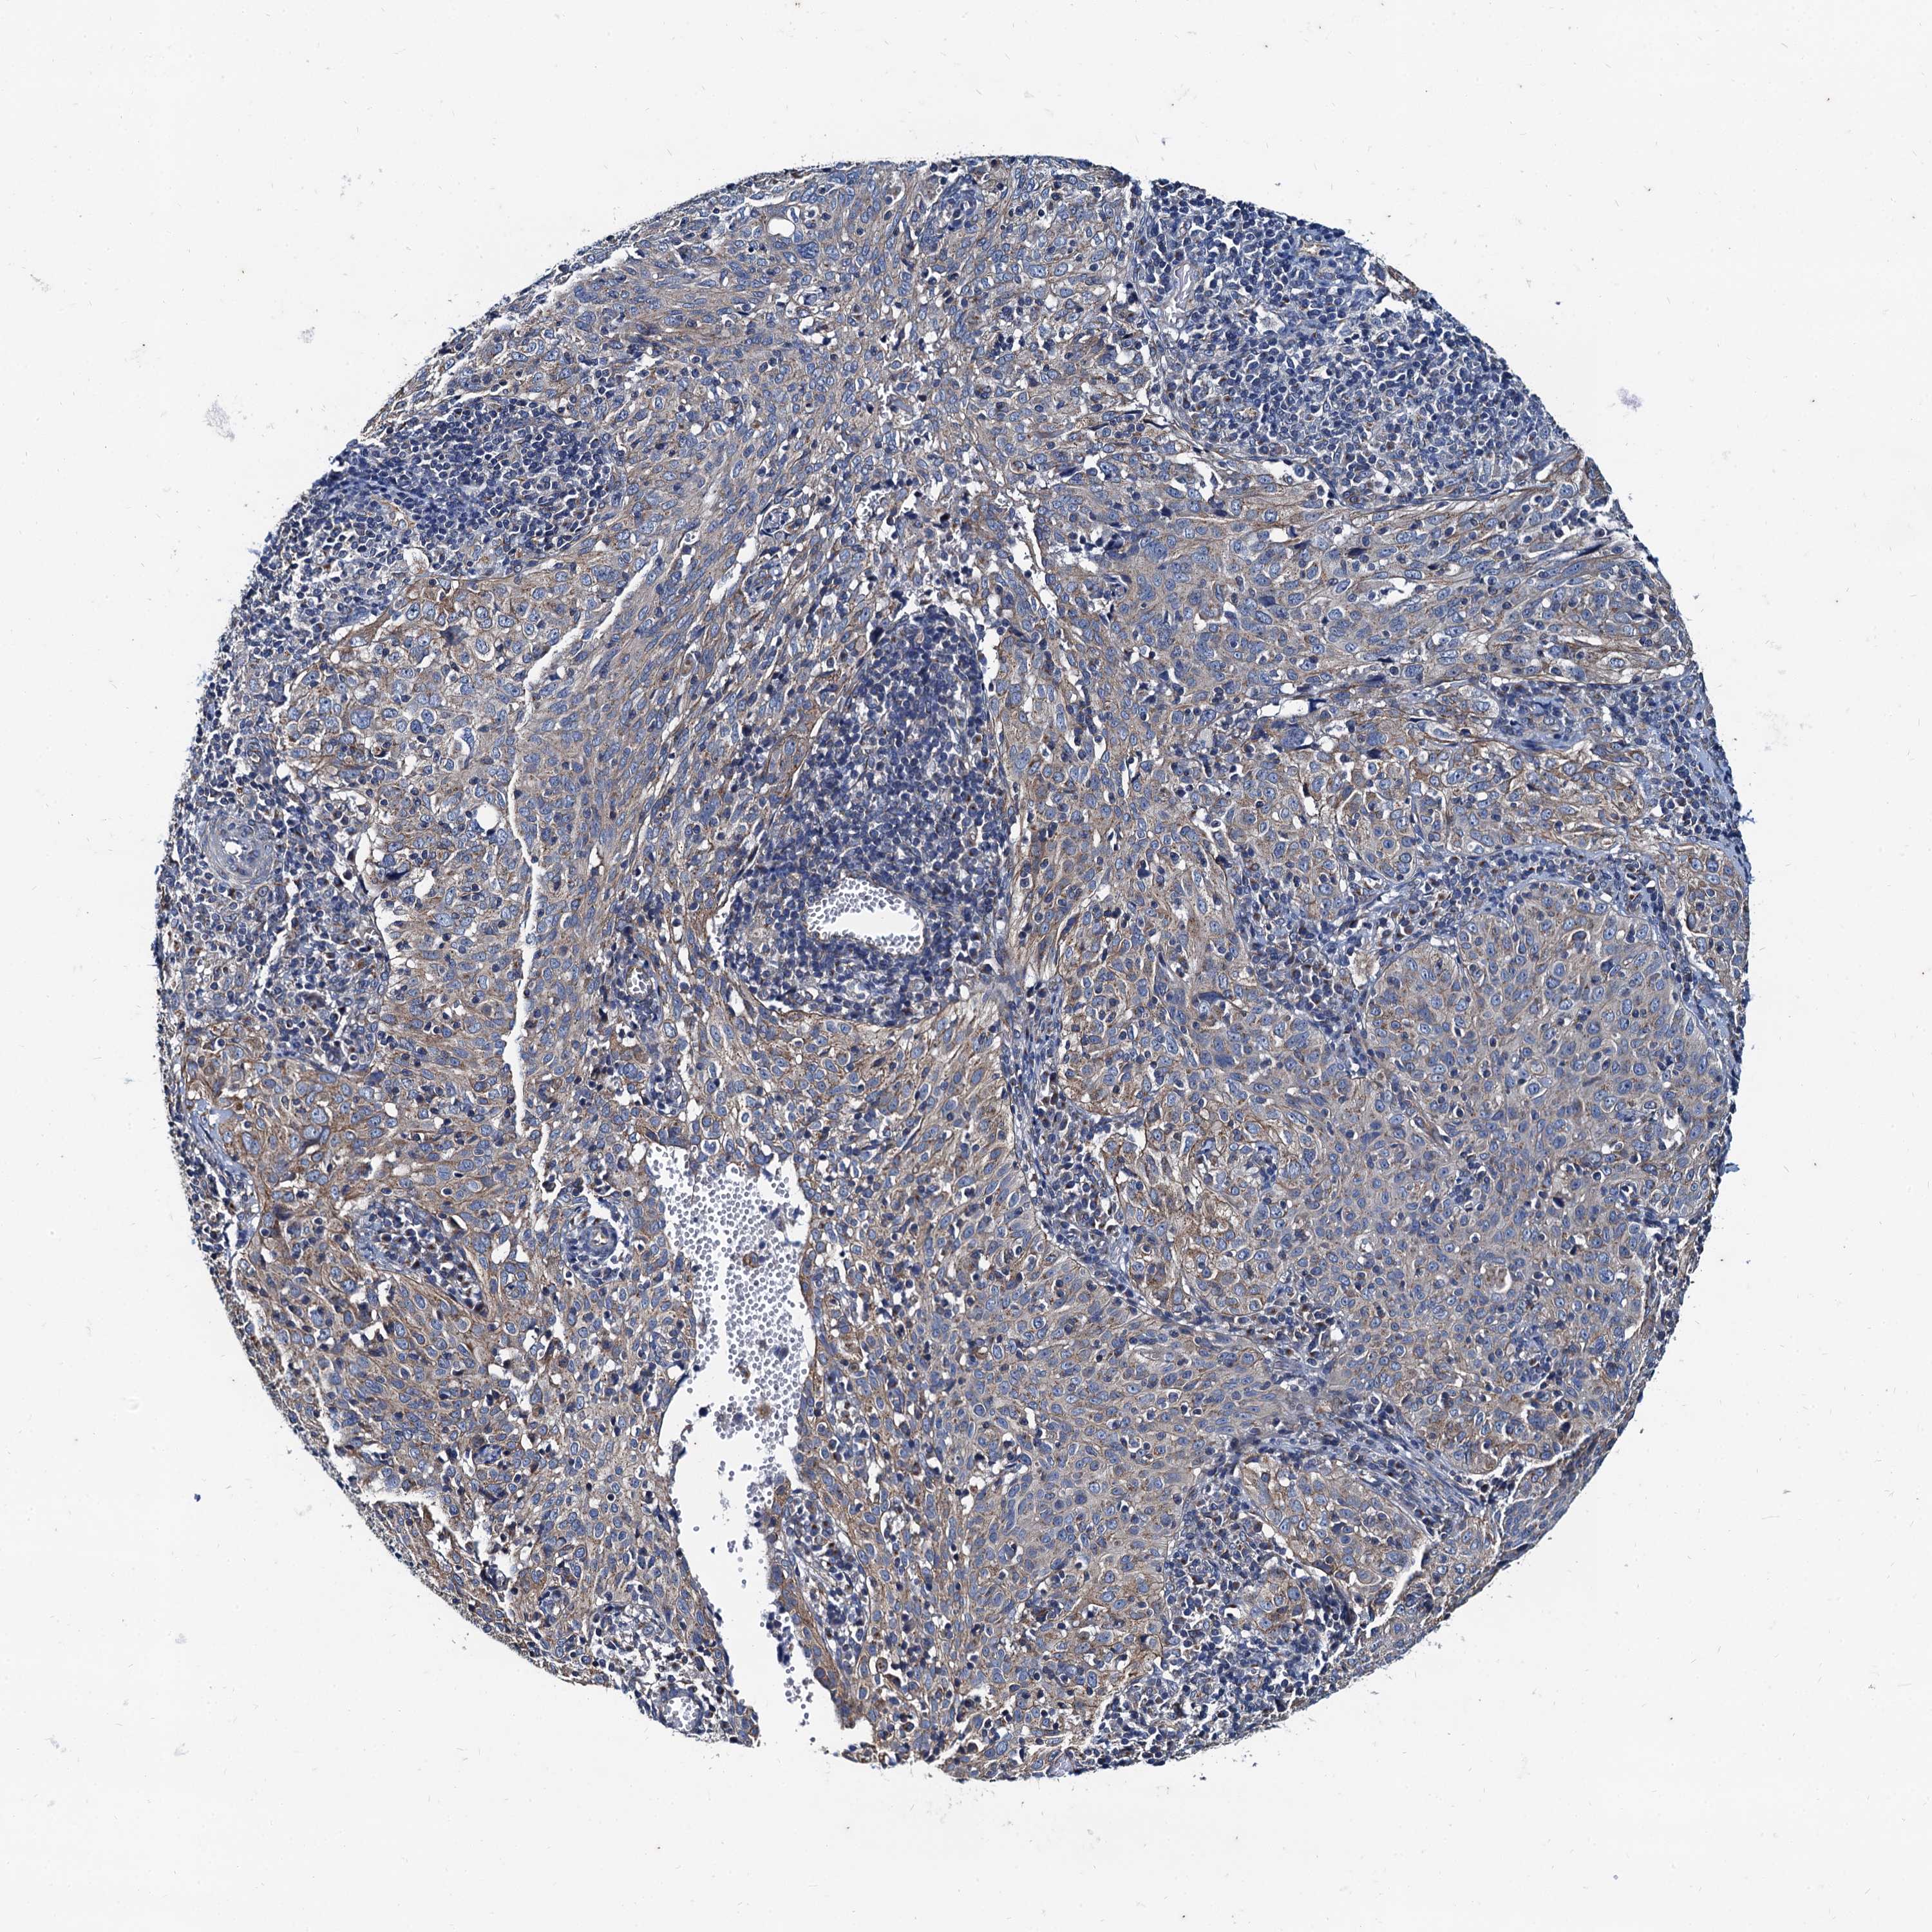

CERVICAL CANCER - Protein expressioni

A mouse-over function shows sample information and annotation data. Click on an image to view it in a full screen mode. Samples can be filtered based on level of antibody staining by selecting one or several of the following categories: high, medium, low and not detected. The assay and annotation is described here.

Note that samples used for immunohistochemistry by the Human Protein Atlas do not correspond to samples in the TCGA dataset.

Antibody stainingi

Antibody staining in the annotated cell types in the current human tissue is reported as not detected, low, medium, or high, based on conventional immunohistochemistry profiling in selected tissues. This score is based on the combination of the staining intensity and fraction of stained cells.

Each image is clickable and will lead to virtual microscopy that enables deeper exploration of all samples and also displays staining intensity scores, fraction scores and subcellular localization as well as patient and tissue information for each sample.

Antibody HPA041367

Antibody HPA076267

Staining

High

Medium

Low

Not detected

Intensity

Strong

Moderate

Weak

Negative

Quantity

>75%

75%-25%

<25%

None

Location

Nuclear

Cytoplasmic/membranous

Cytoplasmic/membranous,nuclear

Squamous cell carcinoma, NOS

Adenocarcinoma, NOS